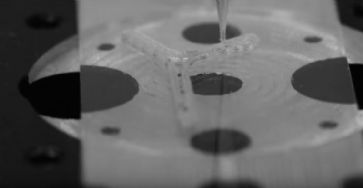

Das Team um Michael McAlpine kombinierte Verfahren der 3D-Bildgebung und des 3D-Drucks, um eine Richtschnur für eine Nervenbahn aus Silikon herzustellen, die - mit biochemischen Informationen versehen - komplexe Nerven wiederherstellt.

In einem ersten Schritt wurde mit einem 3D-Scanner die Struktur des Ischiasnervs einer Ratte nachgebildet. Mit einem speziellen 3D-Drucker wurde dann eine Anweisung für die zu regenerierende Nervenbahn zur Regeneration hergestellt. Anschliessend wurde der neue Nerv an den zuvor gekappten Enden implantiert.